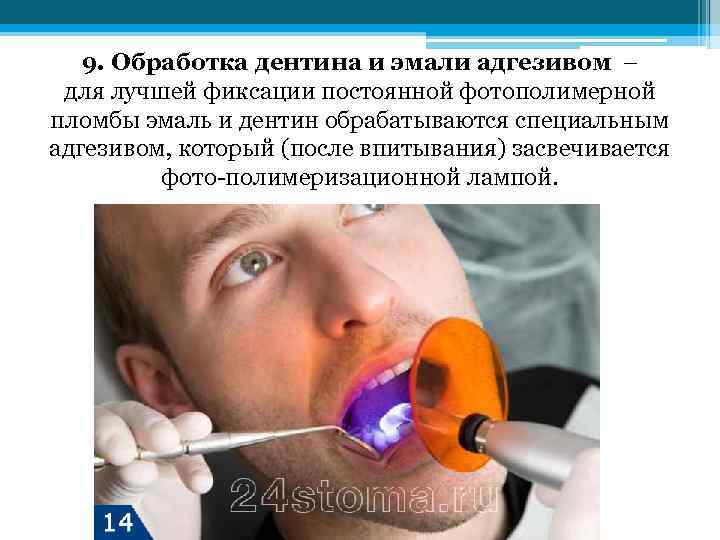

9. Обработка дентина и эмали адгезивом – для лучшей фиксации постоянной фотополимерной пломбы эмаль и дентин обрабатываются специальным адгезивом, который (после впитывания) засвечивается фото-полимеризационной лампой.

9. Обработка дентина и эмали адгезивом – для лучшей фиксации постоянной фотополимерной пломбы эмаль и дентин обрабатываются специальным адгезивом, который (после впитывания) засвечивается фото-полимеризационной лампой.